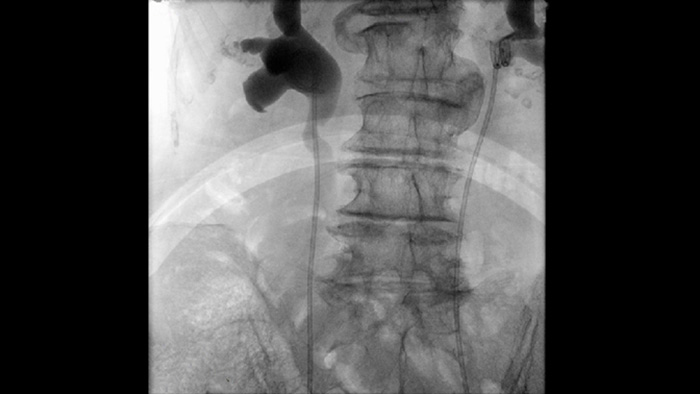

A Fluoroscopia Pulsada aprimora o diagnóstico por imagem de anatomias densas e complexas para apoiá-lo no gerenciamento de doses. Você pode selecionar uma faixa de frequências de pulsos de fluoroscopia para reduzir a dose quando desejar ou aprimorar a qualidade da imagem conforme necessário.

Obturadores assimétricos únicos aumentam a flexibilidade e a precisão da colimação ao permitir que você movimente os obturadores de forma independente e isolados uns dos outros. Você pode ajustar os obturadores e a orientação da imagem enquanto estiver na última retenção de imagem sem usar radiação.